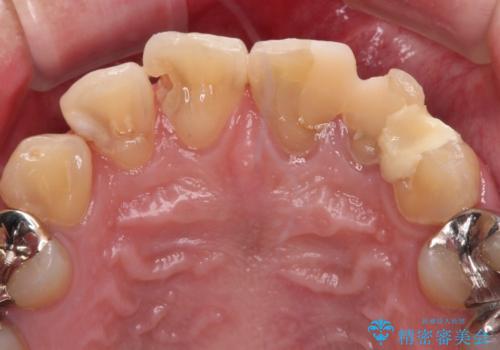

- むし歯の影響で、前歯を見せることが恥ずかしいとのことで来院された患者様です。

全顎的にむし歯が多く、治療が必要な歯はたくさんありましたが、まずは非常に目立つ前歯から処置を行うこととしました。

むし歯は歯肉内にまで進行していると外科処置が必要となりますが、ギリギリの位置でとどまっていたため、速やかにオールセラミッククラウンにて補綴治療することとしました。